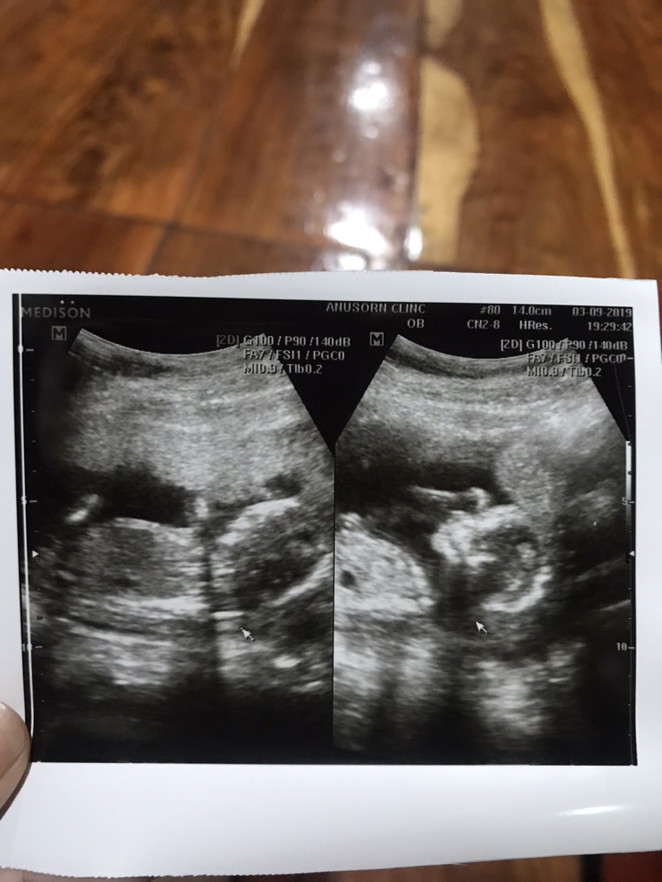

ตอน15weekค่ะ มุมเดียวกันเลย

กำลังจะเข้า5เดือนค่ะ